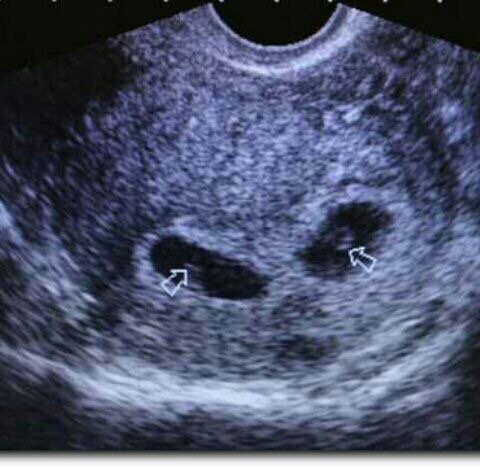

🍁🍂🍁Эта осень застала нас врасплох, встретила приятным сюрпризом… эти два маленьких комочка лежат тут на протяжении 6 недель, но мы ничего не знали. Конечно нас сначала охватил шок учитывая мое положение ..., но мы все равно безумно рады. Особенно от того что их там двое🤣🤣 Я даже не знаю мальчики или там девочки, а может мальчик и девочка. Но бесконечно счастлива…… конечно это может произойти с каждой девушкой, женщиной, и пусть кто мечтает о таком счастье, пусть обязательно будет. ...